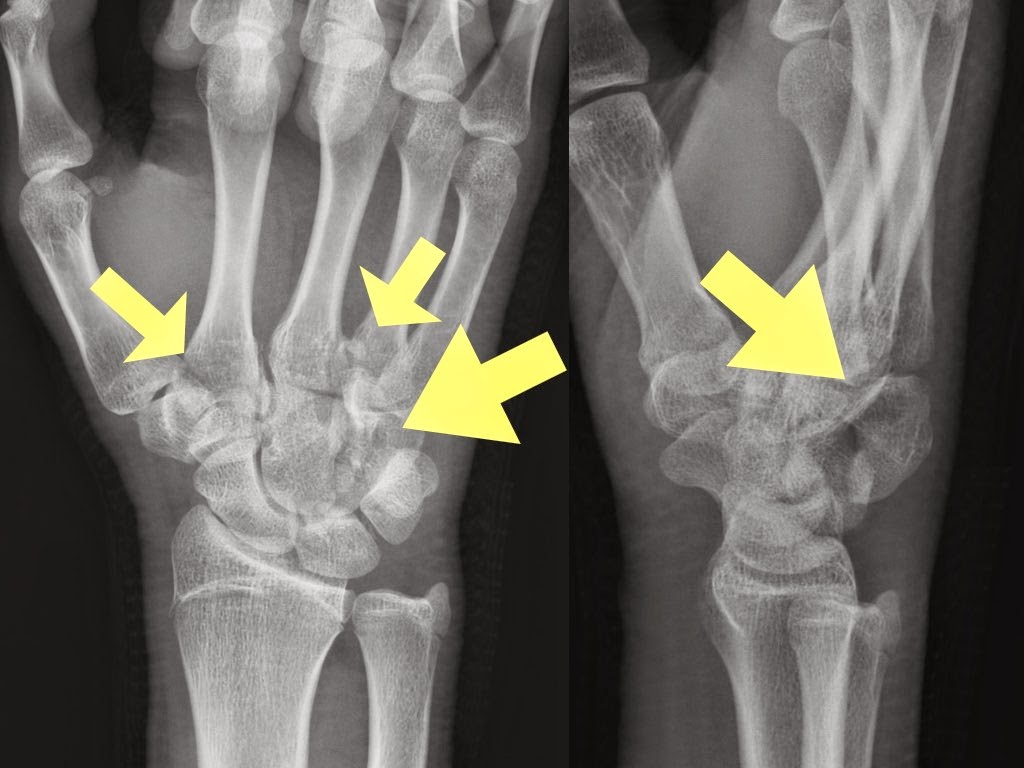

Hamate fracture subluxation Image Hamate Fracture X Ray  Hook of hamate fractures are rare, often missed, injuries generally as a result of a direct blow to the hamate bone most commonly seen in athletes. Diagnosis is generally made with radiographs of the. Hook fractures and body fractures. Hamate body fractures are rare carpal fractures that can be associated with 4th or 5th metacarpal fractures. Radiopaedia.org provides a classification. Hamate Fracture X Ray.

Preoperative xray images Furthermore, CT scans revealed a displaced Hamate Fracture X Ray  Hook fractures and body fractures. Hamate body fractures are rare carpal fractures that can be associated with 4th or 5th metacarpal fractures. Described six radiographic signs that indicate hamate body fracture commonly seen on ap, lateral, and. Hook of hamate fractures are rare, often missed, injuries generally as a result of a direct blow to the hamate bone most commonly. Hamate Fracture X Ray.

(a, b) Xray right wrist PA and lateral views suggestive of a dual Hamate Fracture X Ray  Radiopaedia.org provides a classification of hamate fractures into two types: Hamate body fractures are rare carpal fractures that can be associated with 4th or 5th metacarpal fractures. Hook fractures and body fractures. Described six radiographic signs that indicate hamate body fracture commonly seen on ap, lateral, and. Diagnosis is generally made with radiographs of the. Hamate fractures usually get subdivided. Hamate Fracture X Ray.